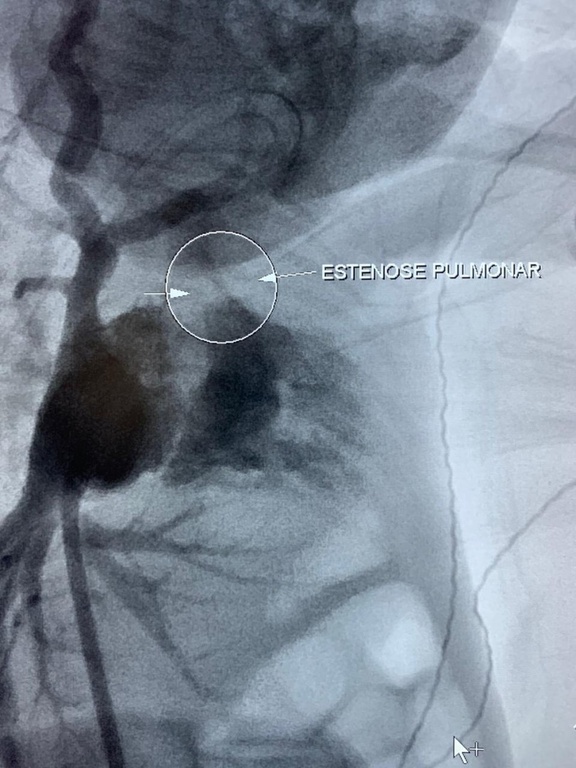

O diagnóstico foi feito ainda no pré-natal: Josafá tinha uma estenose pulmonar (estreitamento do vaso que leva sangue do coração para os pulmões) e a gestação foi levada até a 32ª semana. Josafá nasceu prematuro e foi direto para a Unidade de Terapia Intensiva (UTI) Neonatal. Depois de muitos exames, realizados pela equipe de cardiologia pediátrica do HC-UFU, com apenas dez dias de vida e pesando 1,2 Kg, Josafá passou por um procedimento cirúrgico raro e minimamente invasivo (por vídeo e sem cortes) que permitiu que a circulação sanguínea fosse normalizada.

O procedimento foi realizado pela equipe do Serviço de Hemodinâmica do HC-UFU sob o comando do médico cardiologista e responsável técnico, Vilmar José Pereira. Ele explicou que, normalmente, nas cirurgias cardíacas realizadas por vídeo, utiliza-se as veias mais calibrosas (das pernas, por exemplo) para levar os cateteres até o coração. Como Josafá nasceu prematuro, a equipe utilizou a via umbilical e o acesso ao coraçãozinho foi feito por uma veia no umbigo.

“Foi inserido um cateter da veia umbilical até o coração. Esse cateter tem um balãozinho vazio na ponta. Quando chegou lá na válvula do coração que precisava ser tratada, o balãozinho foi insuflado até aumentar de tamanho e abrir o espaço que precisava para o sangue fluir normalmente”, explicou o cardiologista.